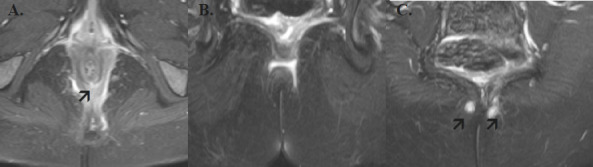

Background: Perianal fistula refers to an abnormal connection between the anal canal and the perianal skin or perineum. Magnetic Resonance Imaging (MRI) plays a crucial role in accurately characterizing perianal fistulas, which informs surgical strategies and helps minimize recurrence.

Results: The study encompassed 304 primary fistula tracts in 276 patients, with 233 (84.4%) being male. Complex fistulas were identified in 83 patients (30.1%), 43 (15.6%) had secondary extensions, and 64 (27.1%) presented with abscess collections. The most common type of fistula, according to the Parks classification, was intersphincteric, observed in 263 cases (86.5%). The St. James University Hospital grades 1 and 2 were predominant, representing 176 (57.9%) and 62 (20.4%) of the cases, respectively. A significant association was found between complex fistulas, higher Parks grades, and the total length of the fistula tract.

Conclusion: This study elucidates MRI patterns of perianal fistulas, revealing that over one-third of patients had complex fistulas. This underscores the importance of preoperative MRI for effective surgical planning and reducing recurrence rates.